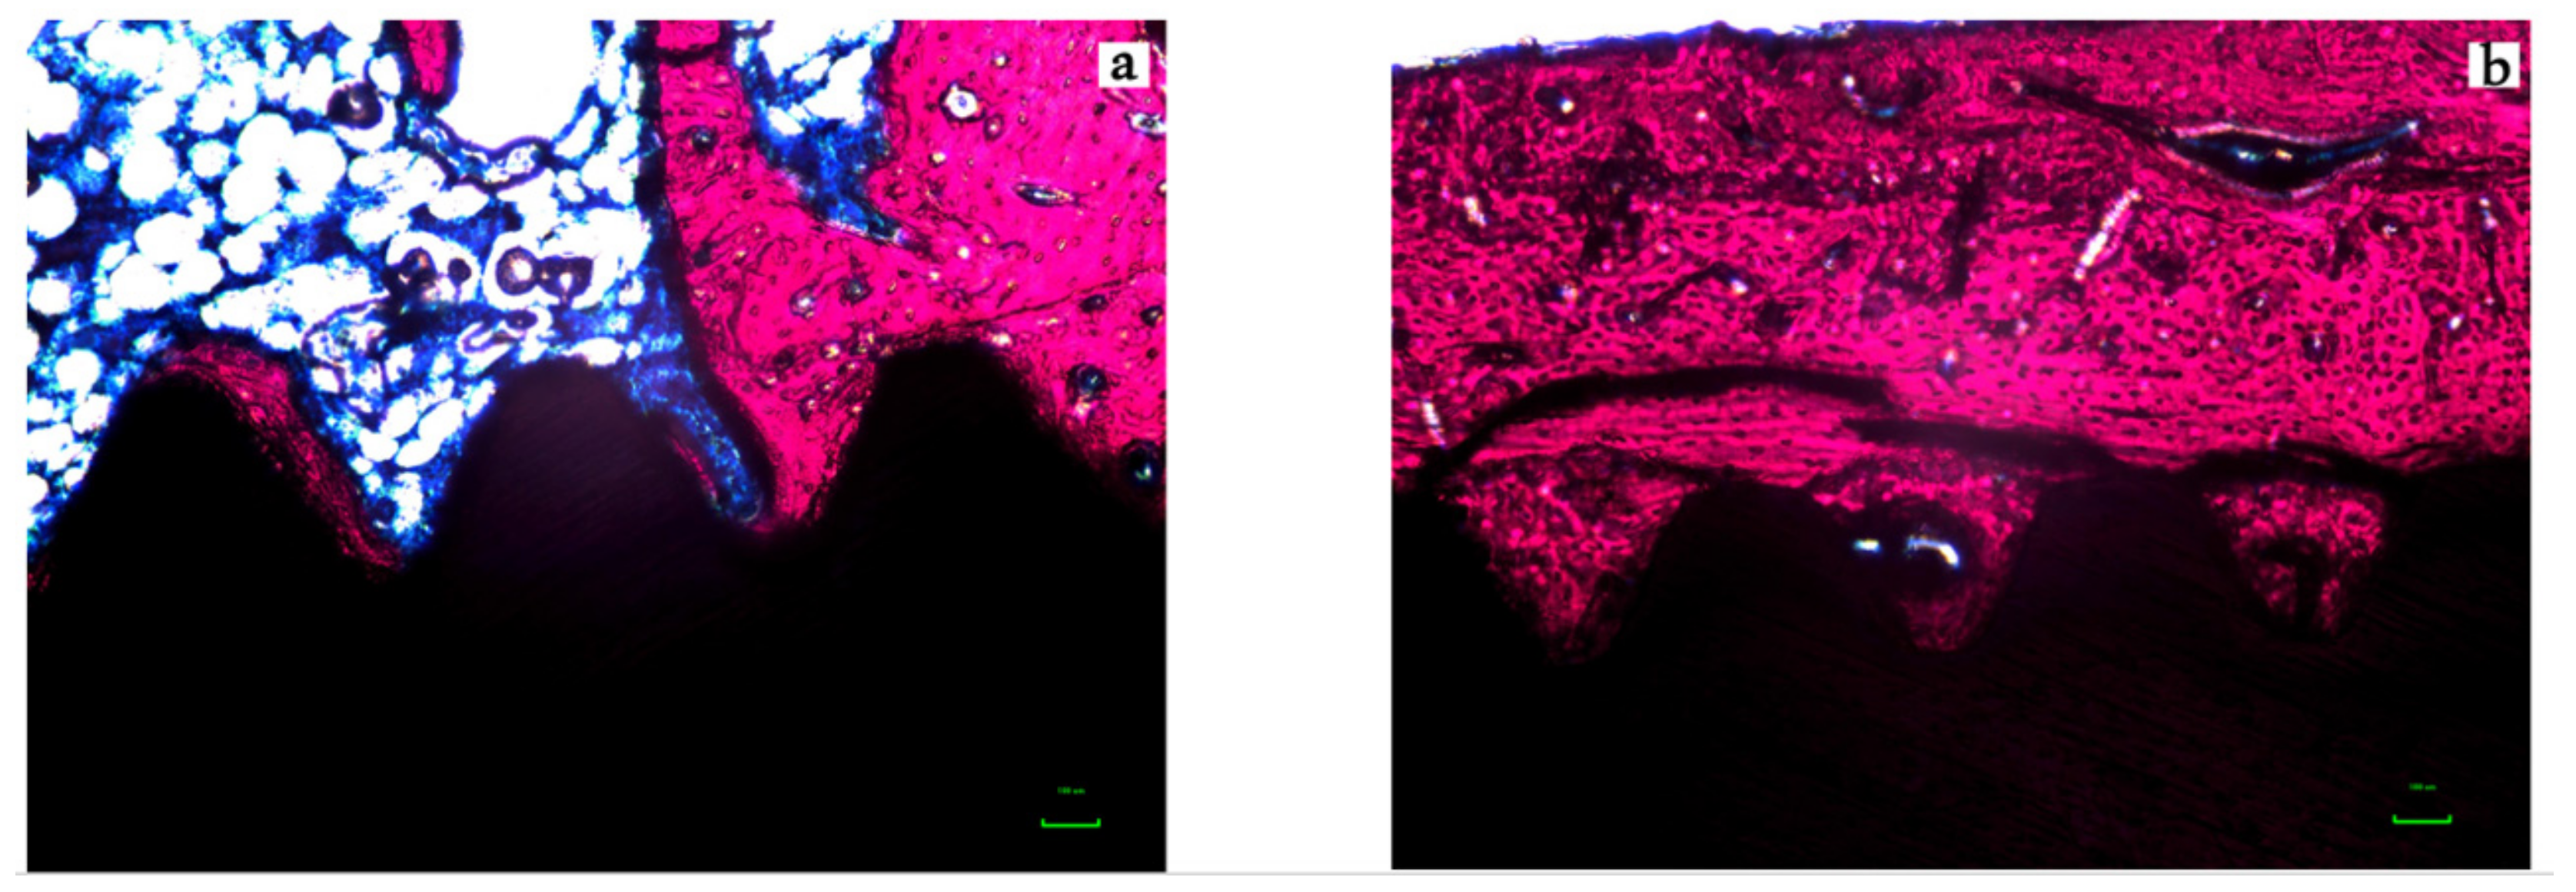

The representative histological images of each group can be seen in Figure 6a,b and Figure 7a,b and the histomorphometric results described above may be more closely visualized in Figure 8.

Figure 6.

Photomicrograph of the micro-implants and surrounding tissues for the Control (A) and Test (B) groups in magnification of 200× (Stevenels’ Blue) for two weeks (T1). Bone mineralized tissue stained in pink, non-mineralized tissue stained in white/blue and titanium in black. Note that the level of bone to implant contact and the bone area occupied between the implants’ threads are higher in the test group.

Figure 7.

Photomicrograph of the micro-implants and surrounding tissues for the Control (A) and Test (B) groups in magnification of 200× (Stevenels’ Blue) for six weeks (T2). Bone mineralized tissue stained in pink, non-mineralized tissue stained in white/blue and titanium in black. Note that the level of bone to implant contact and the bone area occupied between the implants’ threads are higher in the test group.